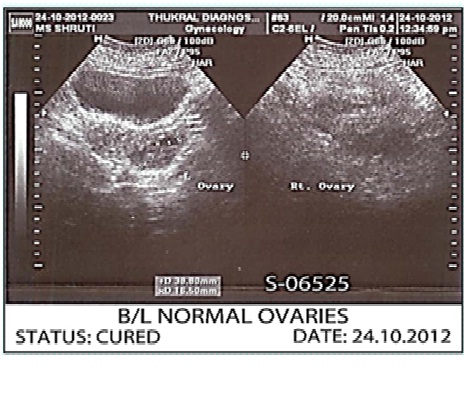

Image: Before Treatment.

A twenty three year old unmarried anaemic girl consulted us for treatment of delayed, scanty menses with phases of amenorrhoea since last 3 years.

She had history of fracture of lower back few years back. Also she had history of suppressions of skin disease by steroidal ointments. She had frequent diarrhoea and vomiting problems in childhood.